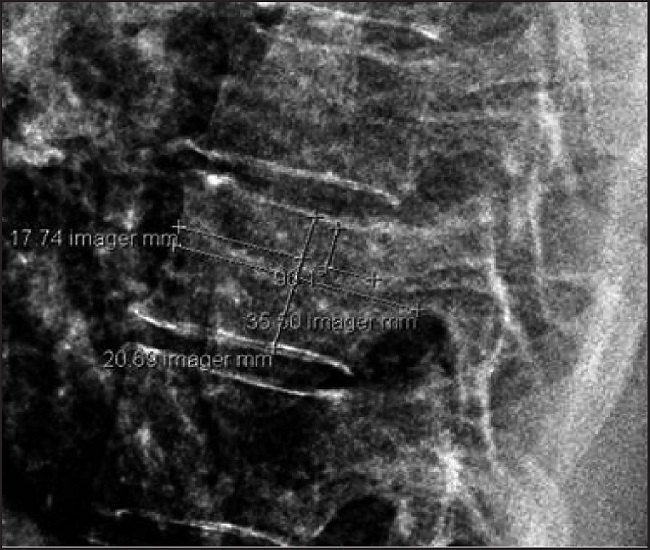

As variables, sex, age, body mass index (BMI), and with a chest lateral plate, not rotated, and in the eighth dorsal vertebra, we calculate his length (LVD8) and his height (HVD8), measured in mm. Figure.

Finally, we applied a comparative study of average of height and vertebral index (VI) results: VI=10 x LVD8/(HVD8 x stature).

Results: 90 patients were analyzed.

20 patients in the study group (222%): 48.1% female, 48.6 years old, 38.2 BMI, and VI 11.6 Meters-1. And 70 patients in the control group (77.8%): 51.1% females 45.15 years old, 26.2 BMI, and VI 11.2 Meters-1. The comparative analysis of avera-ges does not show any significant dif-ferences in the index or in the stature of these patients.

Conclusion: It is a small study, and according to height or the created index, it does not seem that obesity in development modifies the overall height or the vertebral parameters. In addition, the index gives a stable value regarding the sex of both populations in the eighth dorsal vertebra.